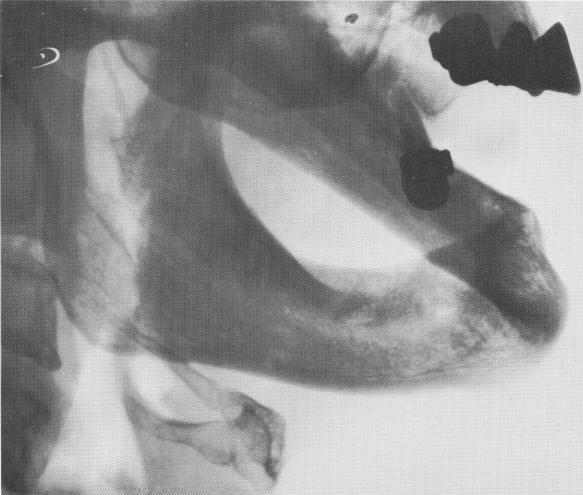

Fig. 2-9. The amount of time elapsing between loss of the teeth and contemplation of an implant intervention is not a sound criterion for judging the amount of alveolar bone remaining. In this totally edentulous mandible, for example, there is more than adequate alveolar bone remaining although the patient may have lost his teeth some time ago. The amount may be caused by the fact that the alveolar process originally consisted of very densely packed bone (as opposed to very loose cancellous bone). Excellent nutrition, no negative bone factor or endocrine gland dysfunctions. Also the habit of chewing directly on the gums may aid bone stimulation. Careful radiography is always a prerequisite before an intervention.

Fig. 2-10. The classification of the mandible for endosseous implant interventions is clearly based upon the amount of alveolar bone remaining. A subperiosteal implant is indicated for C.